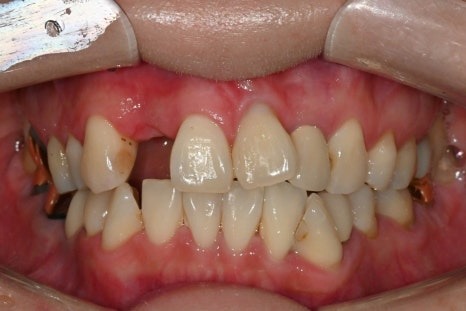

앞니 하나를 빼고 몇달 간 지내셨는데

젊은 여성 환자분이어서

외출하고 다른 사람 만날 엄두를 내지 못할 정도로

불편했다고 하셨습니다.

치아를 발치하고 나면

잇몸뼈가 빠른 속도로 위축되기 때문에

왼쪽 사진처럼 잇몸이

오목한 모양이 되어

심미적이지 못하게 될 뿐더러

음식물이 낄 수도 있습니다.

반대편 같은 위치아 앞니 잇몸처럼

볼록한 모양이 되어야

보기에도 좋기 때문에

임플란트 식립과 더불어

골이식도 동시에 진행하기로 합니다.